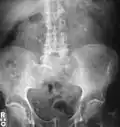

Hvězdovitě tvarovaný kámen v měchýři na RTG pánve. -

Oboustranné ledvinové kameny na RTG snímku. -